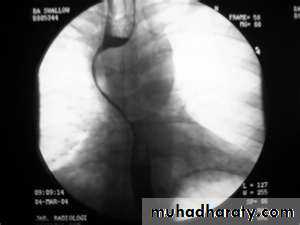

PULSION DIVERTICULUM

Due to:

raised intra-luminal tension

Chocking after meal .

In cervical portion at level of C5

Posteriorly (Killience dehiscent)

Lateral view show increased pre-vertebral space with air fluid level.

Confirmed by Ba. Swallow.

TRACTION DIVERTICULUM

Out pouching of lumen laterally due to fibrosis & adhesions ( post-Tb.)

In the middle third at level of hilum

Up ward direction of diverticulum

Irregular base

On the far left a traction diverticulum (arrow) due to hilar granulomatous disease. Calcified adenopathy (asterisk).

In the middle a pulsion diverticulum (arrow) due to high intra luminal pressure.

On the right multiple pulsion diverticula (arrows)